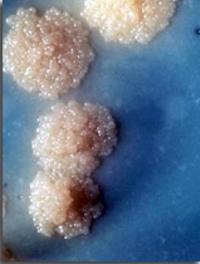

Les infections à Clostridium difficile sont la première cause de diarrhées chez les patients hospitalisés dans les pays développés. [...]

En 1958, une équipe de Denver (Colorado), confrontée à des patients atteints de colites pseudo-membraneuses fulminantes a eu l’idée [...]

Les infections à Clostridium difficile ont la particularité d’être favorisées par les traitements antibiotiques à large spectre et [...]